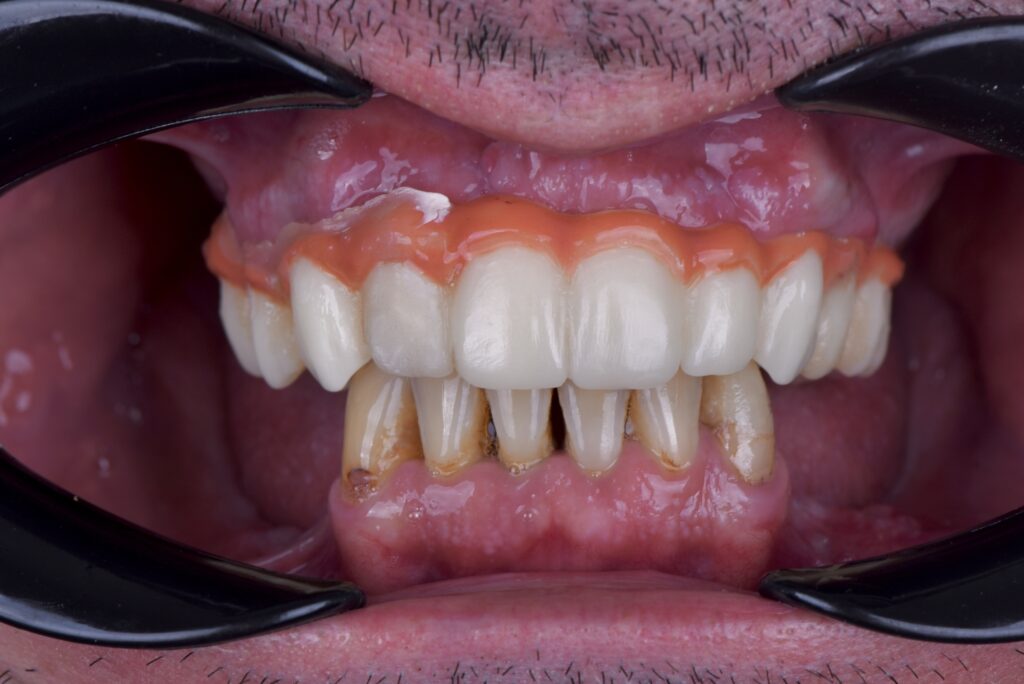

Although a full-mouth rehabilitation using a full upper screw-retained bridge over implants and single crowns over implants on the lower posterior arch, the patients first chose to start with the upper arch.

Fig. 2